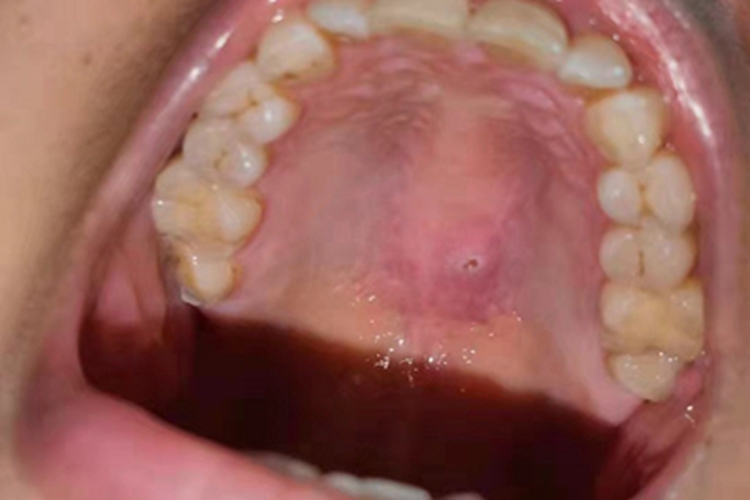

口腔溃疡可累及上腭,可表现为上腭呈片状红肿,中间破溃出现一个小的缺损孔,周围一圈泛白。

口腔溃疡可能与局部的炎症、免疫、感染、系统性疾病及机械、物理、化学刺激因素有关。

对于口腔溃疡上腭有一点破溃的情况,以局部治疗为主。患者可遵医嘱应用复方氯己定含漱液在每次饭后含漱,并外用曲安奈德口腔软膏、重组人表皮生长因子凝胶治疗。病情反复发作的患者,可遵医嘱口服青霉素V钾口含片、显齿蛇葡萄总黄酮含片等药物治疗,并辅以维生素C、维生素B、维生素E、锌制剂治疗。